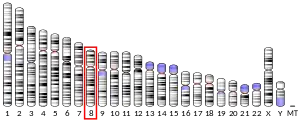

- Hurst J, Flavell D, Julien JP, Meijer D, Mushynski W, Grosveld F (1987). "The human neurofilament gene (NEFL) is located on the short arm of chromosome 8". Cytogenetics and Cell Genetics. 45 (1): 30–32. doi:10.1159/000132421. hdl:1765/2414. PMID 3036423.